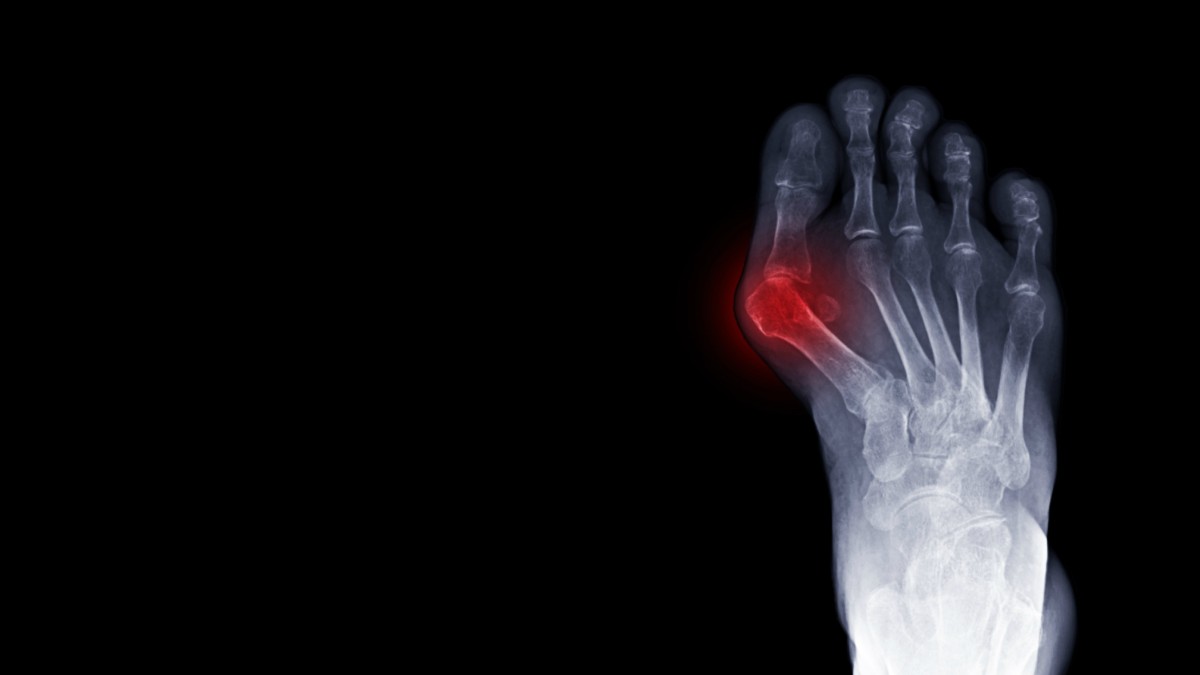

From www.verywellhealth.com

Tailor's Bunion Symptoms, Causes and Treatment What Does A Bunion Look Like On X Ray They may be tender on palpation. Bunionettes are visible on clinical examination as an erythematous swelling overlying the 5 th metatarsal head. Ultrasound is sensitive enough to detect urate crystals in an affected joint. What Does A Bunion Look Like On X Ray.